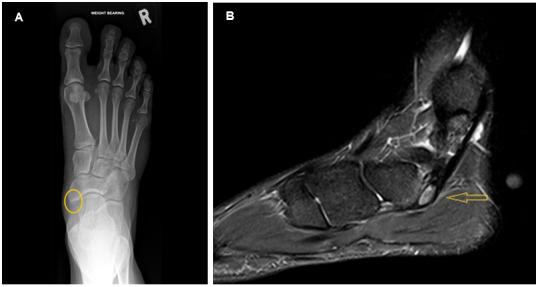

一名22岁女性极限飞盘运动员,患有多囊卵巢综合征(PCOS),表现为慢性足中部疼痛。影像学显示舟舟骨和舟舟副骨骨髓水肿,怀疑是骨应激损伤。保守治疗包括抗炎、减轻负荷、物理治疗、矫形和营养支持。本病例讨论了舟舟副骨,并强调了多囊卵巢综合征与女性运动员骨骼健康之间相互作用的意义。了解这些因素对女性多囊卵巢综合征运动员的损伤预防和最佳管理具有重要意义。

A 22-year-old female ultimate frisbee player, known with polycystic ovary syndrome (PCOS), presented with chronic midfoot pain. Suspecting a bone stress injury, imaging showed bone marrow oedema of the navicular and accessory navicular bones. Conservative management included anti-inflammatories, load reduction, physiotherapy, orthotics and nutritional support. This case discusses the accessory navicular bone and highlights the significance of the interplay between PCOS and bone health in female athletes. Understanding these factors is important for injury prevention and optimal management in female athletes with PCOS.